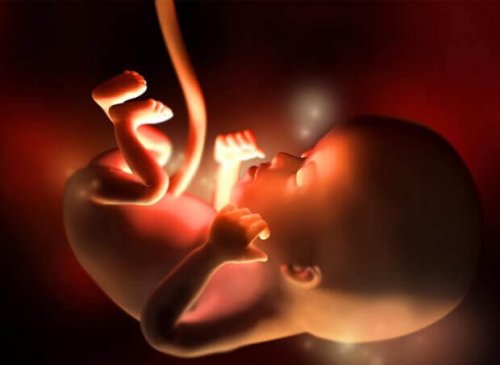

Au cours de la douzième semaine de la grossesse, le dernier du premier trimestre, votre bébé mesurera entre 5 et 6 centimètres et pèsera entre 8 et 14 grammes.

Son cœur bat très fort, à 160 battements par minute, et ses mouvements commencent à se multiplier, même s’ils sont encore imperceptibles pour vous.

La taille de votre bébé est semblable à celle d’une prune ou d’un fruit de la passion à ce stade de la grossesse. En fait, entre la semaine dernière et celle-ci, il a grandi d’environ 15 %.

Ses membres sont déjà formés, les organes commencent à mûrir rapidement et même ses intestins, jusqu’à présent reliés à la base du cordon ombilical, se déplacent vers la cavité abdominale.

De même, sa tête a déjà acquis sa forme arrondie. Sa bouche peut s’ouvrir et se fermer et ses oreilles sont à leur place. Les ongles commencent à être définis, ainsi que les cordes vocales.

Au cours de la douzième semaine de grossesse, les reins commencent à générer de petites quantités d’urine et même les premiers vestiges de poils sur le corps apparaissent.

Bien que le sexe du bébé ne puisse pas encore être différencié par échographie, l’appareil génital est en plein développement à ce stade. De plus, à cette “âge”, le bébé est déjà capable de bâiller, de hocher la tête et d’avaler.